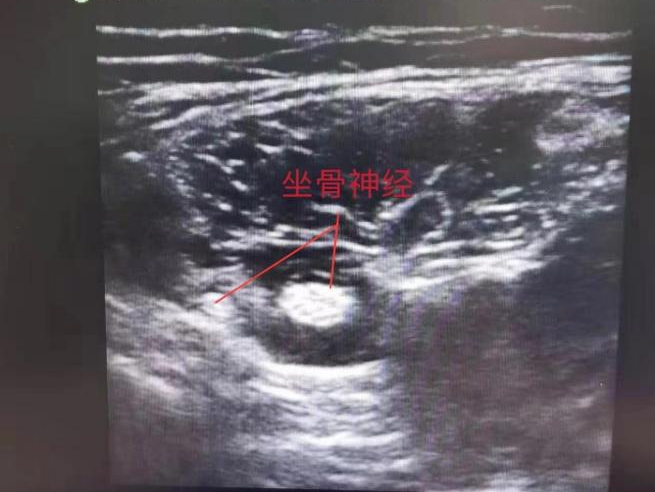

超声引导下神经阻滞麻醉技术 所谓“超声引导下神经阻滞麻醉”,就是麻醉医生借助超声成像技术定位患者的神经位置,然后将局麻药物注射到神经干附近,通过阻断神经冲动的传导,使该神经所支配的区域麻醉,达到精准定位、精准麻醉的效果。神经阻滞的目的就是哪里需要手术就麻醉哪里,是目前麻醉方法中最容易实现精准麻醉的方法。 超声可视化技术号称麻醉科医师的第三只眼睛 “我们接到手术通知后,立即组织开展了术前麻醉方案的讨论。我们考虑到该手术时间长,创伤大,术后疼痛明显。采用常规静吸复合全麻虽然能满足正常手术需要,但术中麻醉药用量大,患儿苏醒时间长且苏醒后由于疼痛会导致苏醒效果差,术后静脉镇痛泵难以无缝衔接。最终,综合考虑后,我们制定了静吸复合麻醉联合超声引导下股神经、坐骨神经阻滞这个方案。该患儿术中和术后的镇痛都取得了非常满意的效果。目前患儿全身情况良好?!笔质趼樽砜聘敝魅吻锘匾涞?。 伴随可视化技术在医学中应用的扩展,超声技术也逐渐走进临床科室中。近些年来超声在临床麻醉中的应用越来越广泛,这些实践不仅可以为麻醉医生在术中及时判断患者的病情带来帮助,更加改变了麻醉医生以往对常规技术理解,改"盲探"为"可见",更加提升了麻醉安全。 钱秋告诉我们:“超声引导下的神经阻滞麻醉技术在成人医院已经趋于普遍和成熟。但是小儿麻醉并非是成人麻醉的"缩小版",在儿童中行神经阻滞麻醉具有更大的挑战。主要原因是:小儿各种神经血管相距非常近,在穿刺的过程中极易对周围组织结构造成损伤;儿童配合性差,无法描述穿刺时的感觉,不能反馈阻滞效果,且儿童用药量较成人更精准严格。此技术在国内尚处于起步发展阶段,只有为数不多的儿童医院常规开展。” 超声引导下的神经阻滞麻醉技术的优势 1、更精准 相较传统的经验阻滞法、按解剖入路阻滞法,超声引导下阻滞更精确。 2、更安全 提高了组织穿刺的安全性,可避免神经副损伤。 3、更高效 减少全身麻醉药尤其是镇痛药的用量,有效的减少了镇痛药物引起的迟发性呼吸抑制等不良反应的发生率。 4、恢复快 有利于患儿术后安全镇痛和快速康复。 吴江区儿童医院麻醉科现已开展超声引导下的神经阻滞麻醉技术,全方位进入了可视化麻醉领域。目前已开展超声引导下臂丛神经、股神经和坐骨神经阻滞约30余例,主要用于四肢畸形矫形和骨折复位等手术及术后镇痛,均取得了良好临床效果和社会反响。 来源:手术麻醉科